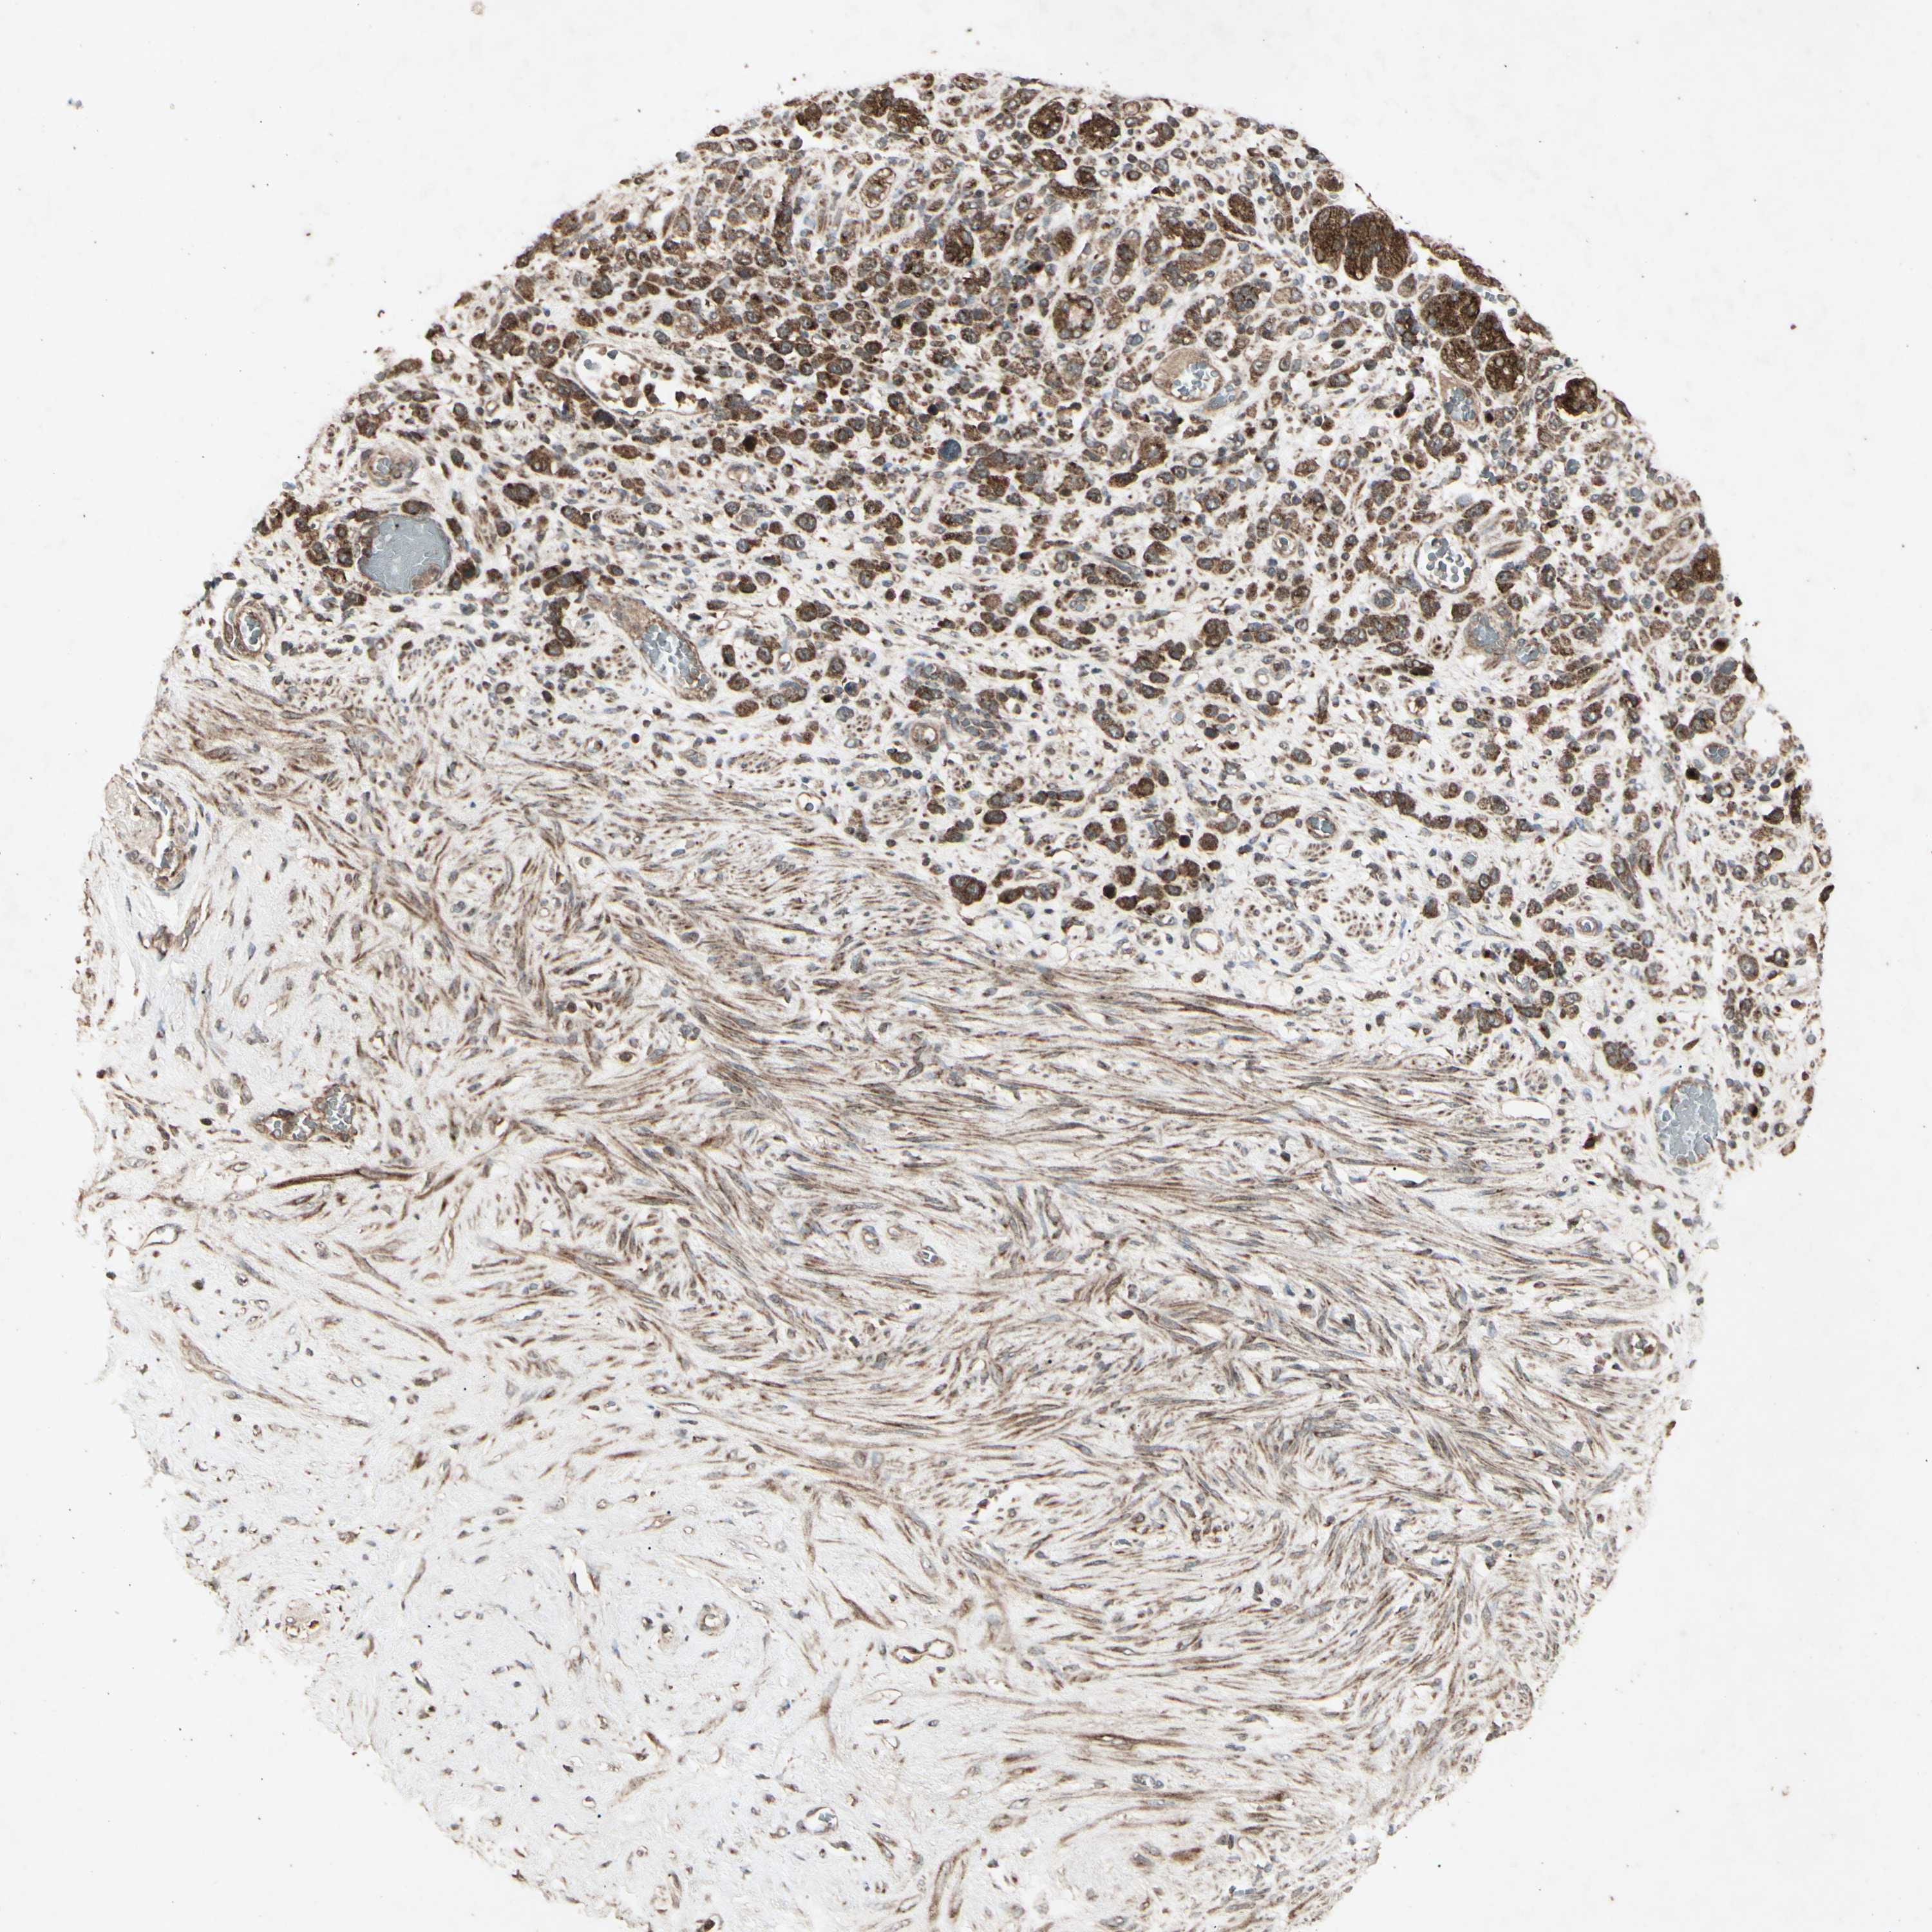

STOMACH CANCER - Protein expressioni

A mouse-over function shows sample information and annotation data. Click on an image to view it in a full screen mode. Samples can be filtered based on level of antibody staining by selecting one or several of the following categories: high, medium, low and not detected. The assay and annotation is described here.

Note that samples used for immunohistochemistry by the Human Protein Atlas do not correspond to samples in the TCGA dataset.

Antibody stainingi

Antibody staining in the annotated cell types in the current human tissue is reported as not detected, low, medium, or high, based on conventional immunohistochemistry profiling in selected tissues. This score is based on the combination of the staining intensity and fraction of stained cells.

Each image is clickable and will lead to virtual microscopy that enables deeper exploration of all samples and also displays staining intensity scores, fraction scores and subcellular localization as well as patient and tissue information for each sample.

Antibody CAB009049

Staining

High

Medium

Low

Not detected

Intensity

Strong

Moderate

Weak

Negative

Quantity

>75%

75%-25%

<25%

None

Location

Nuclear

Cytoplasmic/membranous

Cytoplasmic/membranous,nuclear

Adenocarcinoma, NOS

Adenocarcinoma, High grade